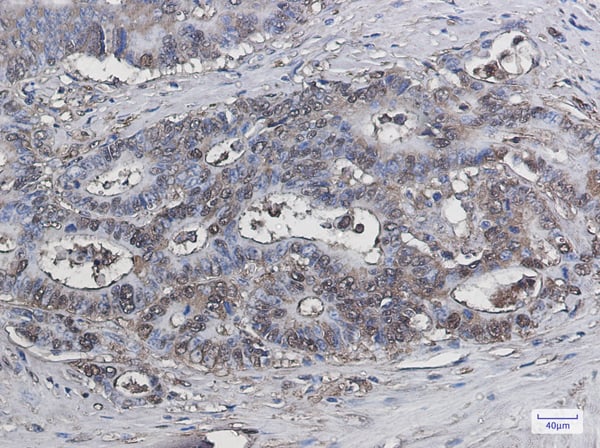

IHC (Immunohistochemisry)

(Immunohistochemical analysis of paraffin-embedded human-colon2 using antibody diluted at 1:50.)